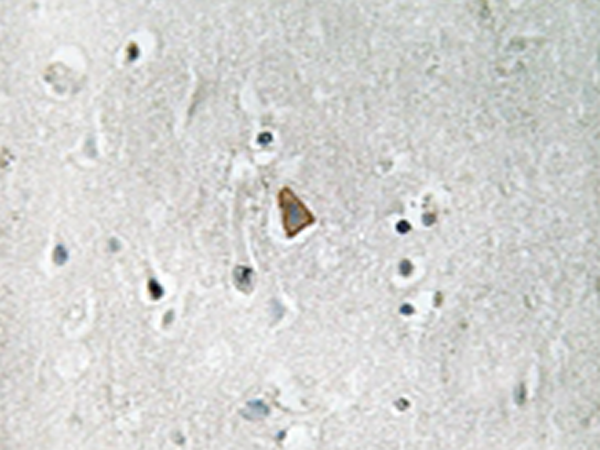

IHC |

IGF1R(Phospho-Tyr1346) |

IHC positive control: |

Human brain tissue |

IHC Recommend dilution: |

50-100 |